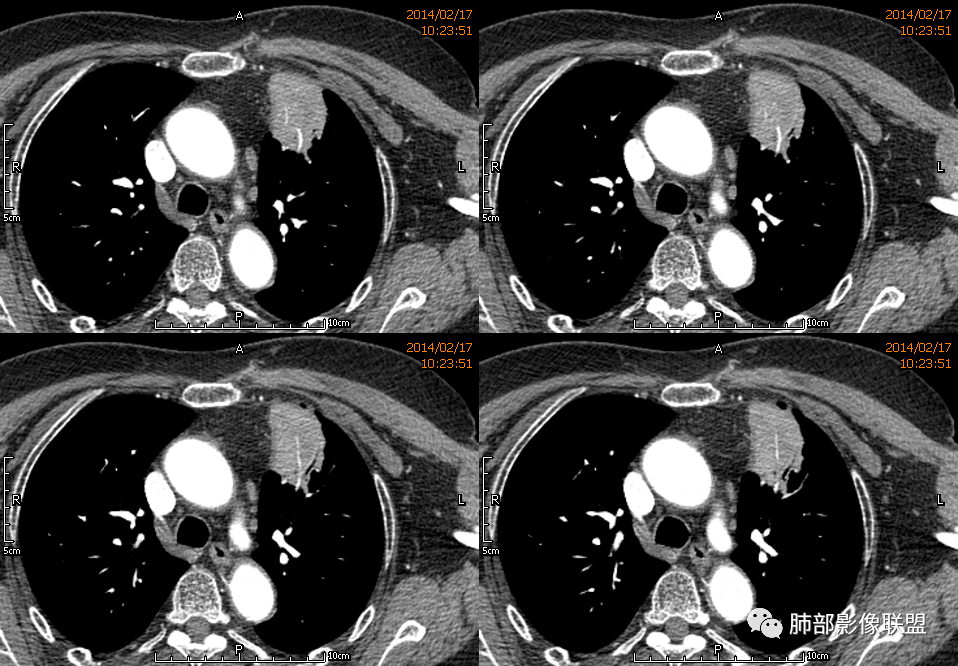

宽基底,附近胸膜增厚,边缘平直

支气管通畅

血管走形自然

坏死灶边界清附近卫星灶

意见:支持炎性。治疗后复查以排除恶性病变隐藏其中

1.块影不规则,未见分叶、毛刺及张力,未见壁结节,肺门纵隔未见肿大淋巴结等,缺少肺腺癌的特征。

2.未见血管及支气管受累,用肺鳞癌不好解释,何况女性患者。

3.病灶易坏死液化,环形强化,支气管及血管贴边进入,“火焰”样边缘轮廓,更符合炎性块影的特点。

4.单发脓肿,临床中毒症状不重,短期多见于肺炎克雷比杆菌感染,亚急性病程的还应排除奴卡菌感染。